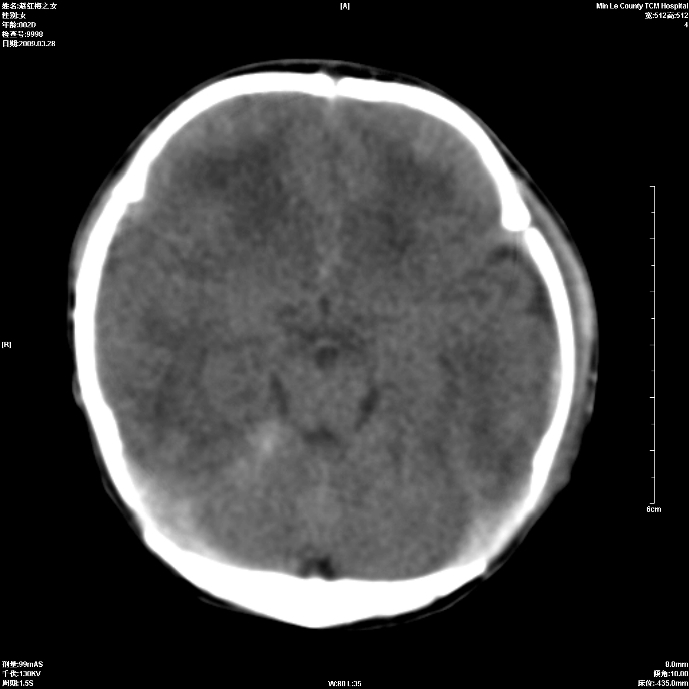

标题: PED1815:患儿出生两天,哭闹不安,囟门饱满 [打印本页]

标题: PED1815:患儿出生两天,哭闹不安,囟门饱满

少量蛛网膜下腔出血,有窒息史吗?

支持考虑新生儿缺血缺氧性脑病伴蛛网膜下腔出血,请结合临床,建议随访复查

缺血缺氧性脑病伴蛛网膜下腔出血.

支持缺血缺氧性脑病伴少量蛛网膜下腔出血。

支持 1)缺氧缺血性脑病。2)蛛网膜下腔出血。

蛛网膜下腔出血

z新生儿缺血缺氧性脑病,蛛网膜下腔出血!